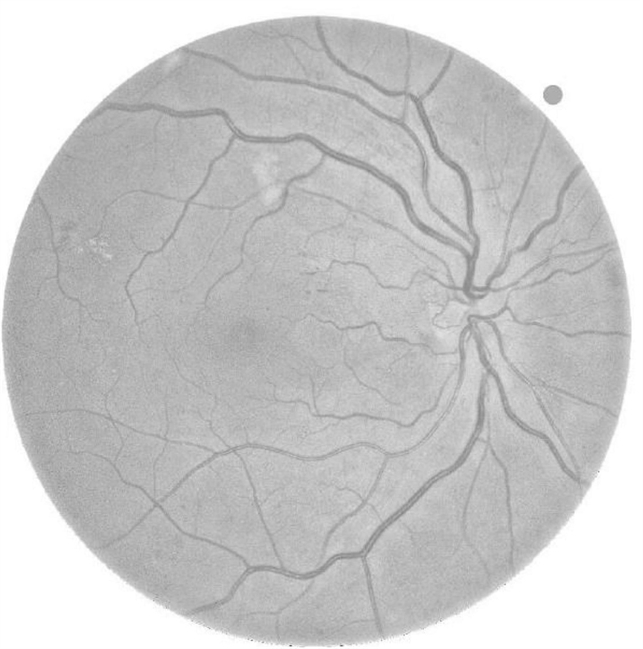

- papillary involvement

- Fundus camera

- 1 MONTH FOLLOW UP FUNDUS IMAGE OF THE SAME PATEINT AFTER GOOD SYSTEMIC CONTROL OF DIABETES. NOTE MARKED REDUCTION OF PAPILLARY RETINOPATHY.